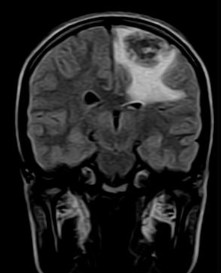

September 2005 - Intracerebral Tuberculomas

There is a conglomeration of lesions in the right temporo-parieto-occipital and left frontal lobes. These are hypointense on the T2W images and reveal a whorl or bunch of grapes type of enhancement. Note is made of perilesional edema.

On MRI

On plain MRI, granulomas usually appear isointense to gray matter on the T1W images and may have a slightly hyperintense rim (probably due to the presence of paramagnetic substances). On T2W images, the tuberculomas exhibit variable signal. They are often isointense or hypointense to brain parenchyma and it is postulated that this relative hypointensity is related to T2 shortening by paramagnetic free radicals produced by macrophages, which are heterogeneously distributed throughout the caseous granuloma. The diminished signal on T2W images may also be due to the mature tuberculoma being of greater cellular density than brain. Granulomas may also be hyperintense to brain on T2-weighted images; this is likely due to a greater degree of central liquefactive necrosis in these lesions. Edema surrounding tuberculomata is relatively more prominent in the early stages of granuloma formation.

Post contrast (gadolinium) images of TB granulomas demonstrate intense nodular and ring-like enhancement. Healed tuberculomas may calcify in up to 20% of cases and these are usually more evident on CT than MRI. On MRI, the calcifications are more evident on gradient-echo than on spin-echo imaging. Atrophy is frequently a long-term sequelae of tuberculous CNS infection. Full resolution of cerebral tuberculomas requires months to years of medical therapy. The length of time required is related more to the size of the original lesion than to any other single factor.